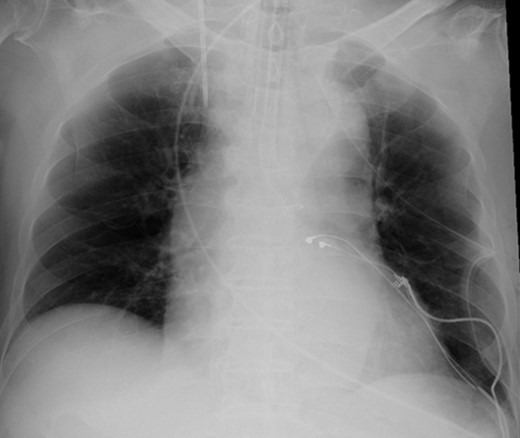

Eight years ago, a DDD pacemaker was implanted in an elderly man due to complete atrioventricular (AV) block. The pacing sites were the appendage of the right atrium and the apex of the right ventricle (Fig. 1) subsequently he suffered PICM with an LV ejection fraction of 37% and obvious dyssynchrony. He had chronic heart failure of NYHA II. Suddenly, the patient developed fever and complained of difficulty eating. Transthoracic echocardiography showed a vegetation (11 × 12 mm2) at the pacemaker leads, and this vegetation was also attached at the tricuspid valve (Fig. 2). Laboratory examination showed elevated white blood cell count and C reactive protein levels. He was diagnosed with PAIE, although the peripheral blood cultures showed no bacteria. After antibiotic therapy, laboratory examination showed decreasing inflammation parameters, but the size of the vegetation remained stable.